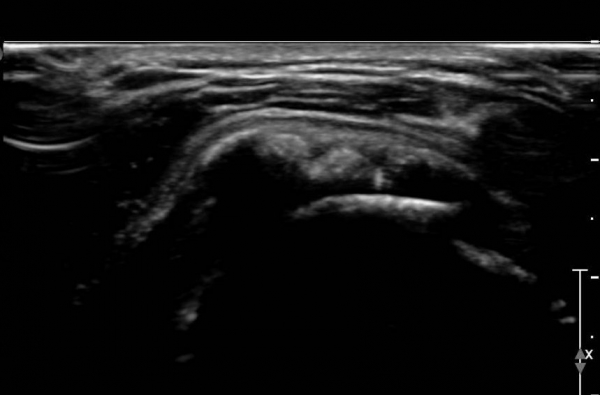

ÃÊÀ½ÆÄ °Ë»ç :  ¿À±¸µ¹±â °ßºÀÀδë Á¾´Ü¸é°Ë»ç¿¡¼­ ÀÎ´ë ½ÉÃþ¿¡ ¼ö¾×Àú·ù°¡ °üÂûµÇ´Âµ¥(»çÁø 1) ÀÌ °ÍÀº

¸¸¼ºÀûÀÎ Ãæµ¹ÁõÈıºÀ» ¾Ï½ÃÇÑ´Ù.